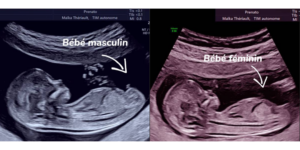

À ce stade précoce, il est important de savoir que les organes génitaux du fœtus ne sont pas encore complètement formés. Tous les foetus présentent un petit bourgeon génital, aussi appelé tubercule génital. L’angle de ce bourgeon, par rapport à leur colonne vertébrale, peut donner une indication sur le sexe biologique :

– Garçon : le bourgeon pointe vers le haut, avec un angle supérieur à environ 30° par rapport à sa colonne vertébrale.

– Fille : le bourgeon est à l’horizontale ou pointe vers le bas, avec un angle inférieur à 30° par rapport à sa colonne vertébrale.